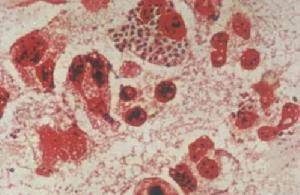

2.形態與染色淋球菌呈卵圓形或豆形,菌體長0.6~0.8μm,寬約0.5μm。常成對排列,鄰近面扁平或稍凹陷,像兩粒豆子對在一起。無鞭毛,不形成芽孢。在急性感染的機體內,其形態較典型,多位於細胞漿內。慢性期則在細胞外。淋球菌革蘭染色陰性。用鹼性美藍染色時,菌體呈藍色。用PappehheimSaathof染色時,菌體呈紅色,背景為天藍色,十分清晰。淋球菌在人工培養基上有五種不同的菌落形態,分別稱為T1,T2,T3,T4,T5,其中T1和T2有毒力,T3和T4無菌毛,不能感染人類。

(4)病變形成:淋球菌侵人黏膜下層後繼續增殖,約在36h內繁殖一代。通過其內毒素脂多糖、補體和IgM等協同作用,形成炎症反應,使黏膜紅腫。同時,由於白細胞的聚集和死亡,上皮細胞的壞死與脫落,出現了膿液。腺體和隱窩開口處病變最為嚴重。